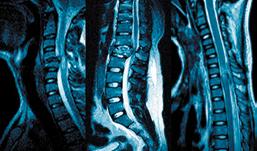

En los últimos años, el desarrollo científico y tecnológico ha transformado significativamente la Medicina. En el campo de la columna vertebral, la introducción de tecnologías como la tomografía computarizada y la resonancia magnética ha revolucionado el diagnóstico, mientras que los avances en implantes para estabilizar la estructura vertebral han ampliado las opciones de tratamiento.

Además, las técnicas de mínima invasión, la robótica y la inteligencia artificial están brindando nuevas posibilidades tanto en diagnóstico como en tratamiento, lo que subraya la necesidad de una formación especializada y continua para los médicos ortopedistas y neurocirujanos.

El consenso mundial de expertos en cirugía de columna reconoce que la etapa moderna de la cirugía se inicia con el uso de los nuevos elementos para estabilizar la estructura vertebral. Como mencioné anteriormente, en la Clínica de Columna iniciamos aplicando técnicas que estaban probadas para la escoliosis. Utilizamos halos cefálicos para tracción cervical, lo que nos permite lograr la reducción temprana de luxaciones cervicales; también empleamos

En la actualidad utilizamos todo tipo de implante de acuerdo a la necesidad del tratamiento; consideramos que las variedades de acceso a la estructura vertebral por cualquier plano anatómico y las técnicas de mínima invasión con o sin lentes, con lentillas o microscopio etc. deben ser consideradas únicamente como “modus operandi” para alcanzar el fin propuesto.